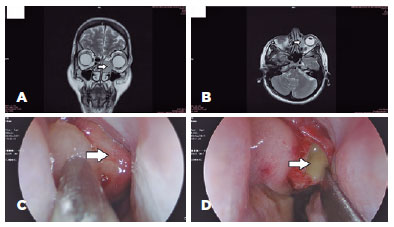

Optical coherence tomography (OCT) revealed macular elevation (Figure 1B). Orbital ultrasonography (USG) detected the T-sign (Figure 1C). An ethmoidal mucocele that compresses the orbital tissues was detected in the magnetic resonance imaging of the orbit (Figures 2A and B). We decided to refer the patient to the department of otorhinolaryngology. Rigid nasoendoscopy revealed left ethmoidal cystic lesion (Figure 2C).

06-fig02.jpg)

Examinations results indicated an ethmoidal mucocele with orbital compression, and transnasal endoscopic marsupialisation and drainage were performed (Figure 2D).